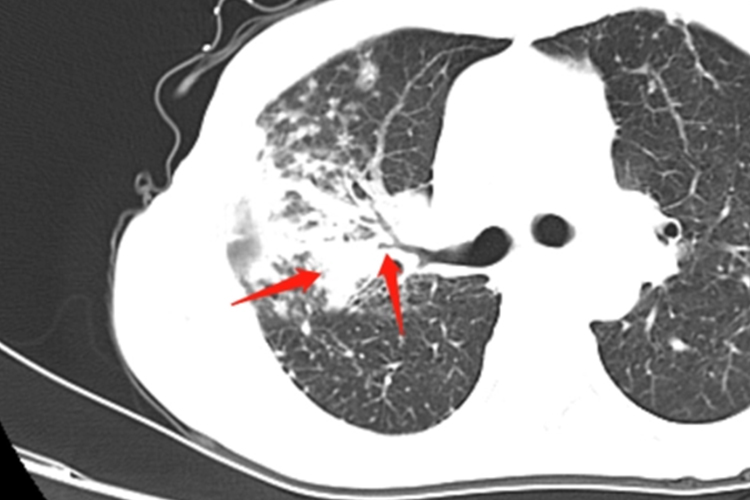

继发性肺结核:具体表现多样,如斑片影、空洞、结核球等。影像学可出现局限性斑片影,见于两肺上叶尖段、后段和下叶背段,还可有肺段或肺叶大片致密性实变,其内可见一个或多个空洞,为虫蚀样空洞,边缘模糊。结核球为圆形椭圆形影,大小0.5-4cm不等,多为2-3cm,边缘清晰,轮廓光滑。